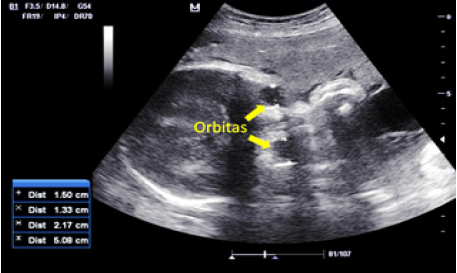

Un continuo control prenatal y en evaluaciones perinatales sucesivas persiste megavejiga de llenado parcial de 44 x 33 mm, de paredes engrosadas, hidronefrosis bilateral (12 mm), micropene (Figura 3), escroto vacío, polidactilia postaxial en manos y onfalocele secundario a megavejiga (Figura 4).

En el tercer trimestre de la gestación es referida a la Unidad de Perinatología de la maternidad de alto riesgo de la Ciudad Hospitalaria “Dr. Enrique Tejera”, donde se evalúa a las 32 semanas de gestación constatando los hallazgos antes descritos además de microftalmia (Figura 5), y arteria umbilical única (Figura 6), se solicita evaluacion prenatal por cardiología pediátrica y la ecocardiografía fetal concluye corazón estructuralmente sano.